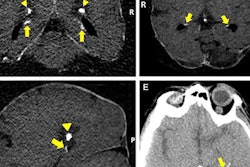

A 60-year-old man known to have HIV presented with seizures. The solid calcifications on noncontrast enhanced CT (NCECT) at the right frontal (left), left basal ganglia (middle), and right parietal areas (right) represent sequela following treatment for documented toxoplasmosis. All images courtesy of Dr. Froilan Celzo.

Same patient: Coronal (left) and sagittal (right) 3D reconstructions are shown.Also known as cerebral calculi, brain stones may be extra- or intra-axial in location. Extra-axial brain stones comprise tumors and exaggerated physiological calcifications, while intra-axial calcifications can be classified under neoplastic, vascular, infectious, congenital, and endocrine/metabolic etiologies, they wrotein an article published online on 11 September by Insights into Imaging.